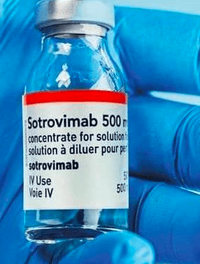

Les anticorps monoclonaux occupent une place importante dans le traitement de la Covid-19. Certains d’entre eux réduisent le risque [...]

REGEN-COV, initialement connu sous le nom de REGN-COV2, est la combinaison de deux anticorps monoclonaux neutralisants, respectivement [...]